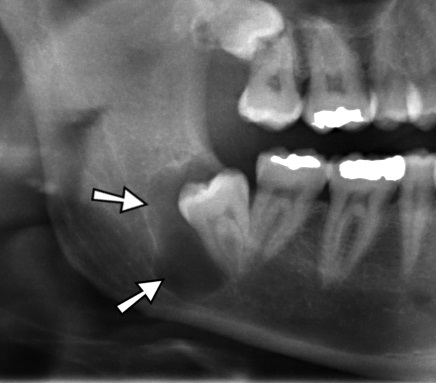

• Appears as a radiolucent area surrounding the crown of unerupted or impacted tooth.

• It can be differentiated from normal follicular space (3-4 mm), when the size of radiolucency is more than 5 mm.

• Description : Dentigerous jaw cyst in the right mandible around and impacted wisdom tooth.